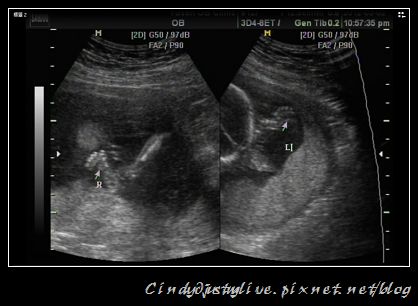

看完頭圍肚圍再來就是要看他的四肢,看手掌、腳掌有沒有都正常五隻,寶寶很不配合,手都一直只給看一隻,另一隻手都擋住了不好看,後來醫生一直搖我肚子,要寶寶起來動一動,換個姿態讓他可以看清楚一點!

寶寶不理他,只好先看腳丫子囉!

醫生說很難得可以看的到寶寶的兩隻腳,一般都是只能看到一邊而已,所以給他來了張大腳丫照片。

拍完腳之後,醫生又搖了我肚子一陣,終於寶寶才給面子的翻身讓他看小手了,幸好一切正常!